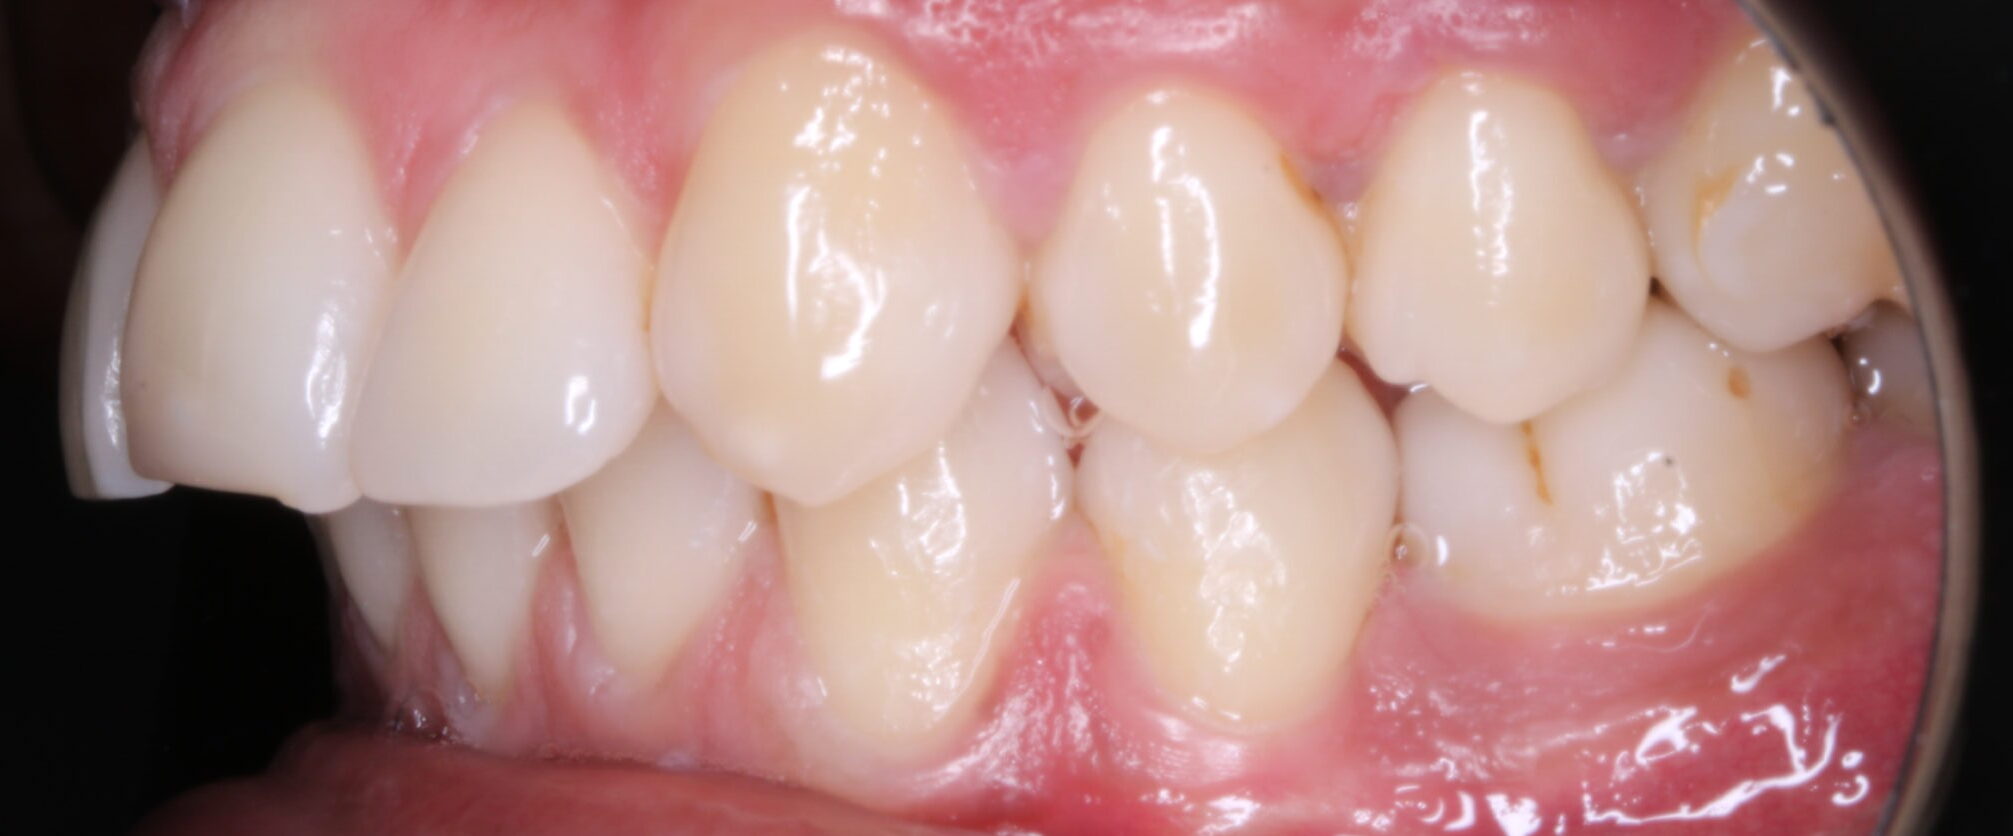

FOTOGRAFÍAS DE INTERÉS